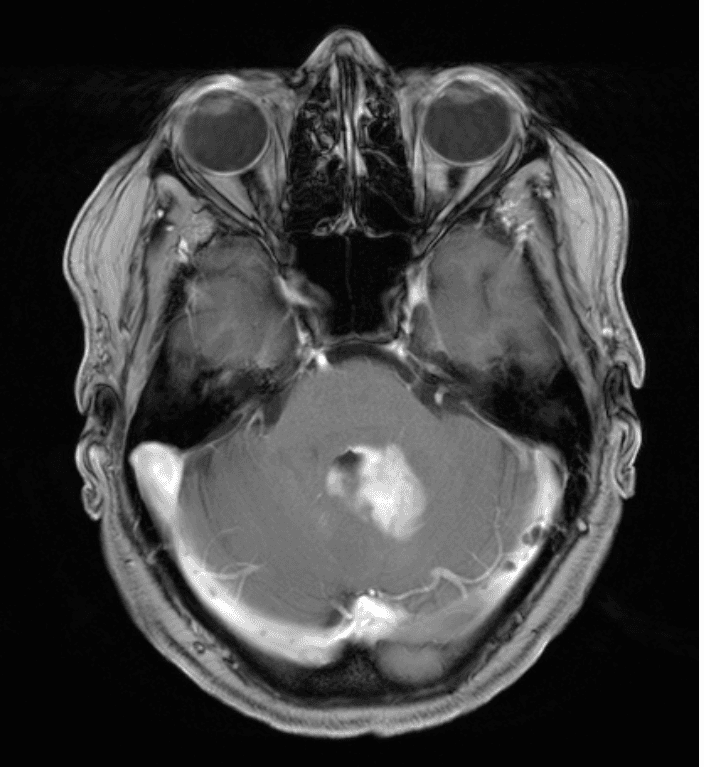

Ha effettuato una risonanza magnetica che ha mostrato una lesione omogenea con contrasto adiacente al quarto ventricolo nel tessuto cerebellare e un edema perifocale moderato (Figure 1–2). I peduncoli del tronco encefalico e cerebellari non erano coinvolti. Non sono stati rilevati segni di emorragia o ischemia.

Figura 2. Questa vista assiale mostra un'iperintensità periventricolare T2, che mostra un edema perifocale moderato. Il lume del quarto ventricolo è ancora aperto, permettendo il passaggio del liquido cerebrospinale. Si prega di notare l'assenza di un effetto di massa significativo o di segni di ernia transtentoriale.Se non trattata, questa lesione porterebbe infine a idrocefalo oclusivo, coma e la morte. Se la dimensione aumentasse, i sintomi cerebellari aumenterebbero (ad esempio, disartria, tremore intenzionale, attassia) e i sintomi del tronco encefalico probabilmente peggiorerebbero (deficit dei nervi cranici, ad esempio, difficoltà a deglutire, paresi, disregolazione vegetativa, coma).